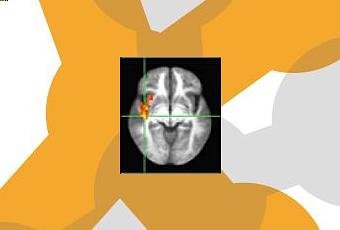

· Les modèles d’activité dans les régions du cerveau responsables de la réactivité émotionnelle, la cognition et les sensations corporelles (interoception) ont également réduits, selon les examens

d’IRM (Voir schéma ci-contre) : Les militaires américains qui ont reçu une formation à la pleine conscience (rouge) présentent une activité réduite dans l’insula ou cortex insulaire, une zone du cerveau qui agit comme un connecteur. Des schémas « types » déjà observés chez les athlètes de haut niveau et les forces spéciales de la Marine américaine, les Navy SEALs.

Une forte activité dans ces zones est, a contrario, associée à l’anxiété et aux troubles de l’humeur.